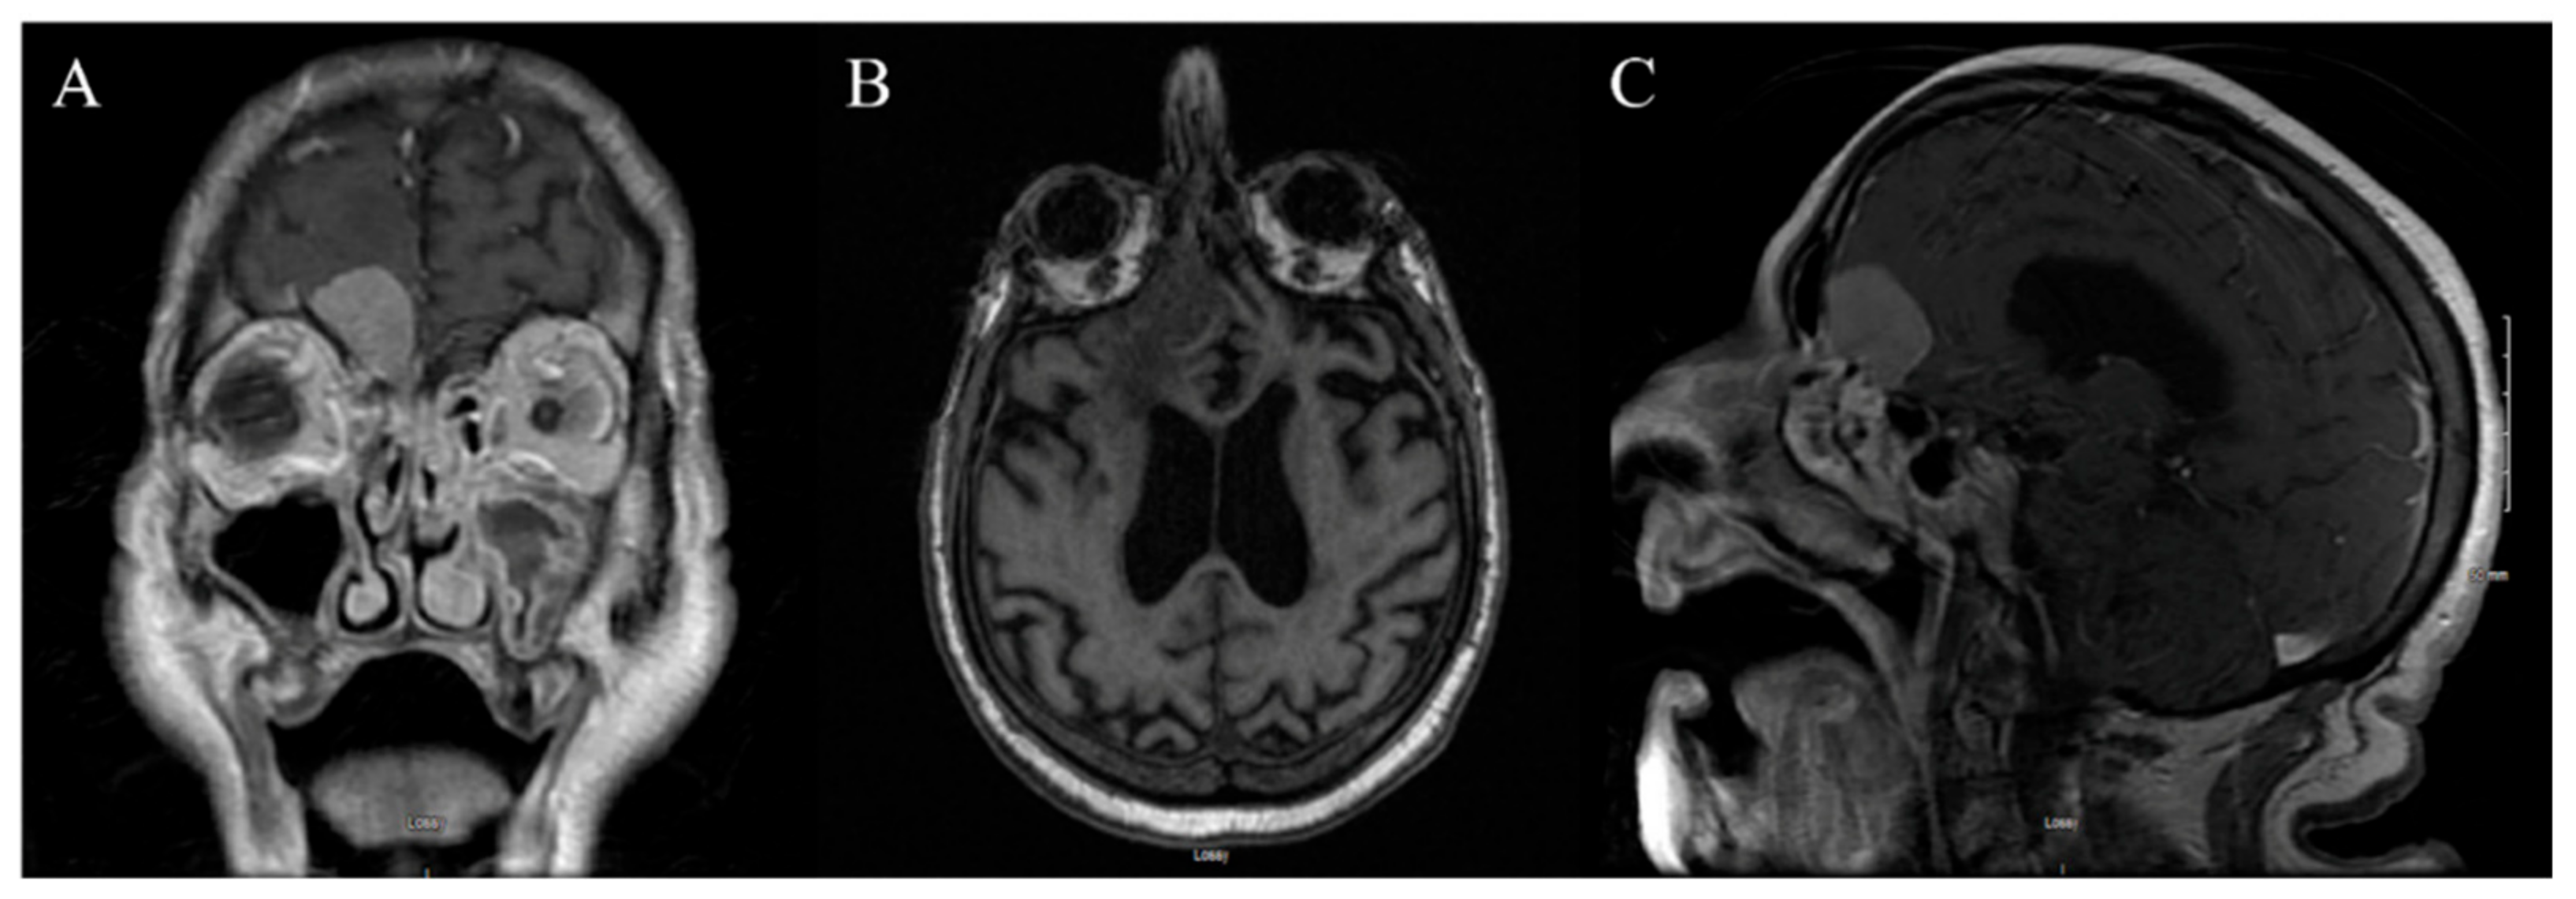

3.1. Case 1

3.1.1. Demography, Presentation, and Evaluation

3.1.2. Intervention

3.1.3. Postoperative Period